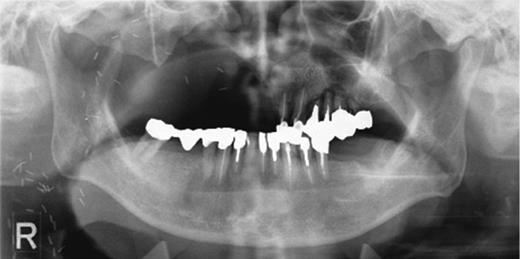

Preoperative orthopantomography. Molar teeth on the left side had been previously extracted because of severe periodontitis.

The patient used a jaw prosthesis with clasps over the remaining left maxillary teeth. However, these teeth were not strong enough to support a large jaw prosthesis that would cover the right maxillary defect, and residual teeth were missing. The patient sought implant treatment in the left maxillary molar region. However, computed tomography (CT) revealed that the bone mass of the left molar region was inadequate for implantation of these fixtures (Fig. 2). We performed the sinus-lift procedure under local anesthesia. The soft tissue from the canine region to the molar tooth region was incised and elevated to expose the underlying lateral wall of the left maxillary sinus. A 12 × 5 mm window was created in the bone of the maxillary sinus anterior wall with a piezoelectric instrument to expose the underlying Schneiderian membrane, which is the lining of the maxillary sinus cavity. Through careful instrumentation, the membrane was carefully peeled from the inner aspect of the sinus cavity (Fig. 3a). No damage to the membrane of the maxillary sinus was present. The newly formed space within the bony cavity of the sinus inferior to the intact membrane was grafted with artificial bone, and artificial bone was placed on the alveolar crest to raise the alveolar crest (Fig. 3b). The gingival flap was replaced and sutured to complete the sinus-lift procedure. There was minimal hemorrhage during the operation, and hemostasis was adequate. There was insignificant facial swelling immediately after the operation.